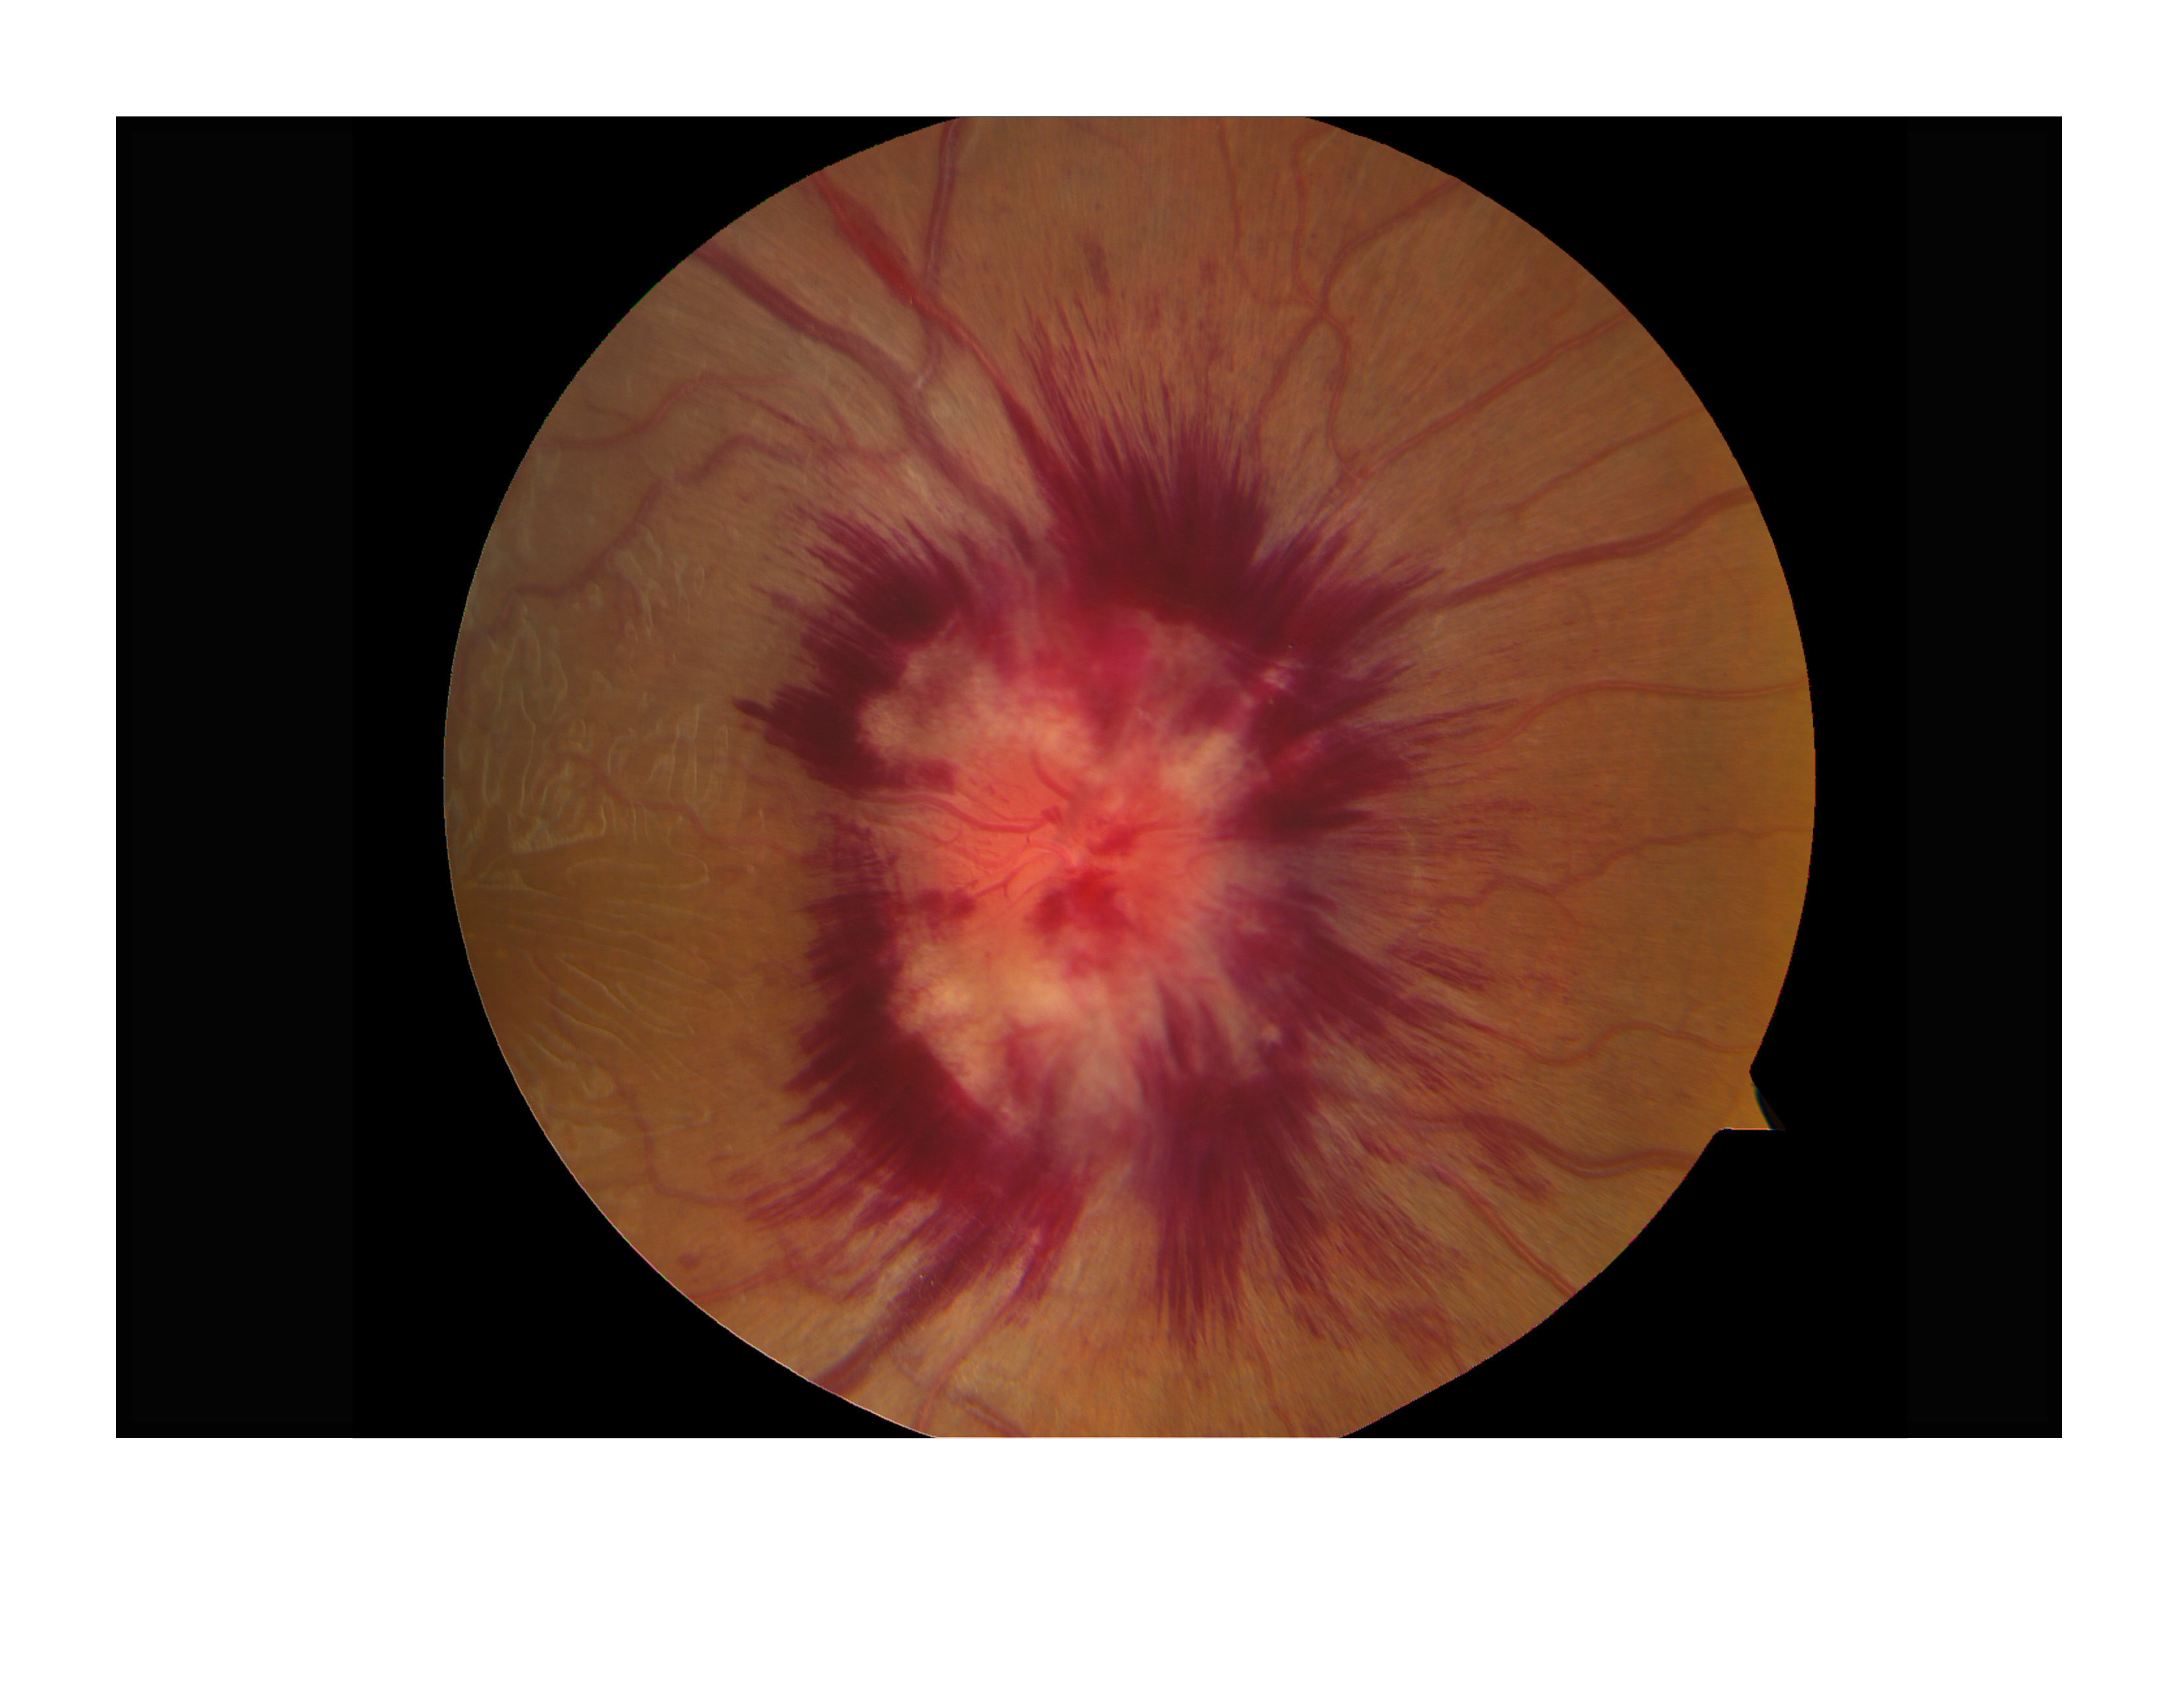

IR Papilledema Presented by Eileen Frommer This photograph received Second Place in the category "Fundus Photography - High Magnification" and was displayed in the 2024 OPS Exhibit. Filed Under Retina OPS Photo